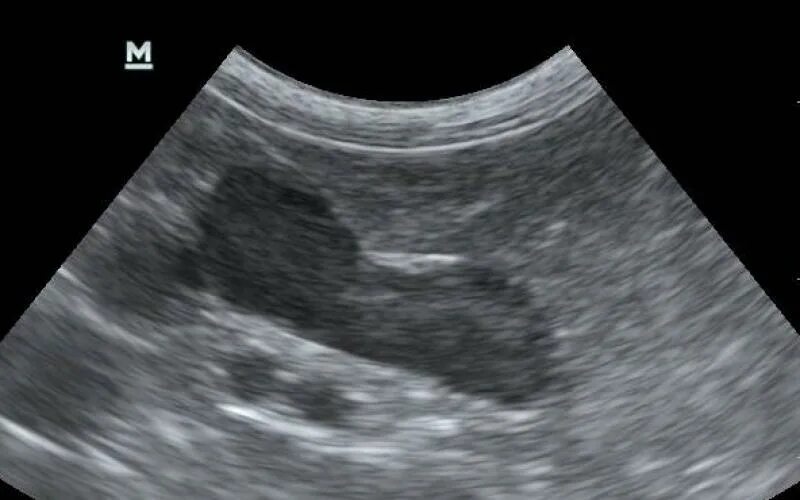

Надпочечники у собаки